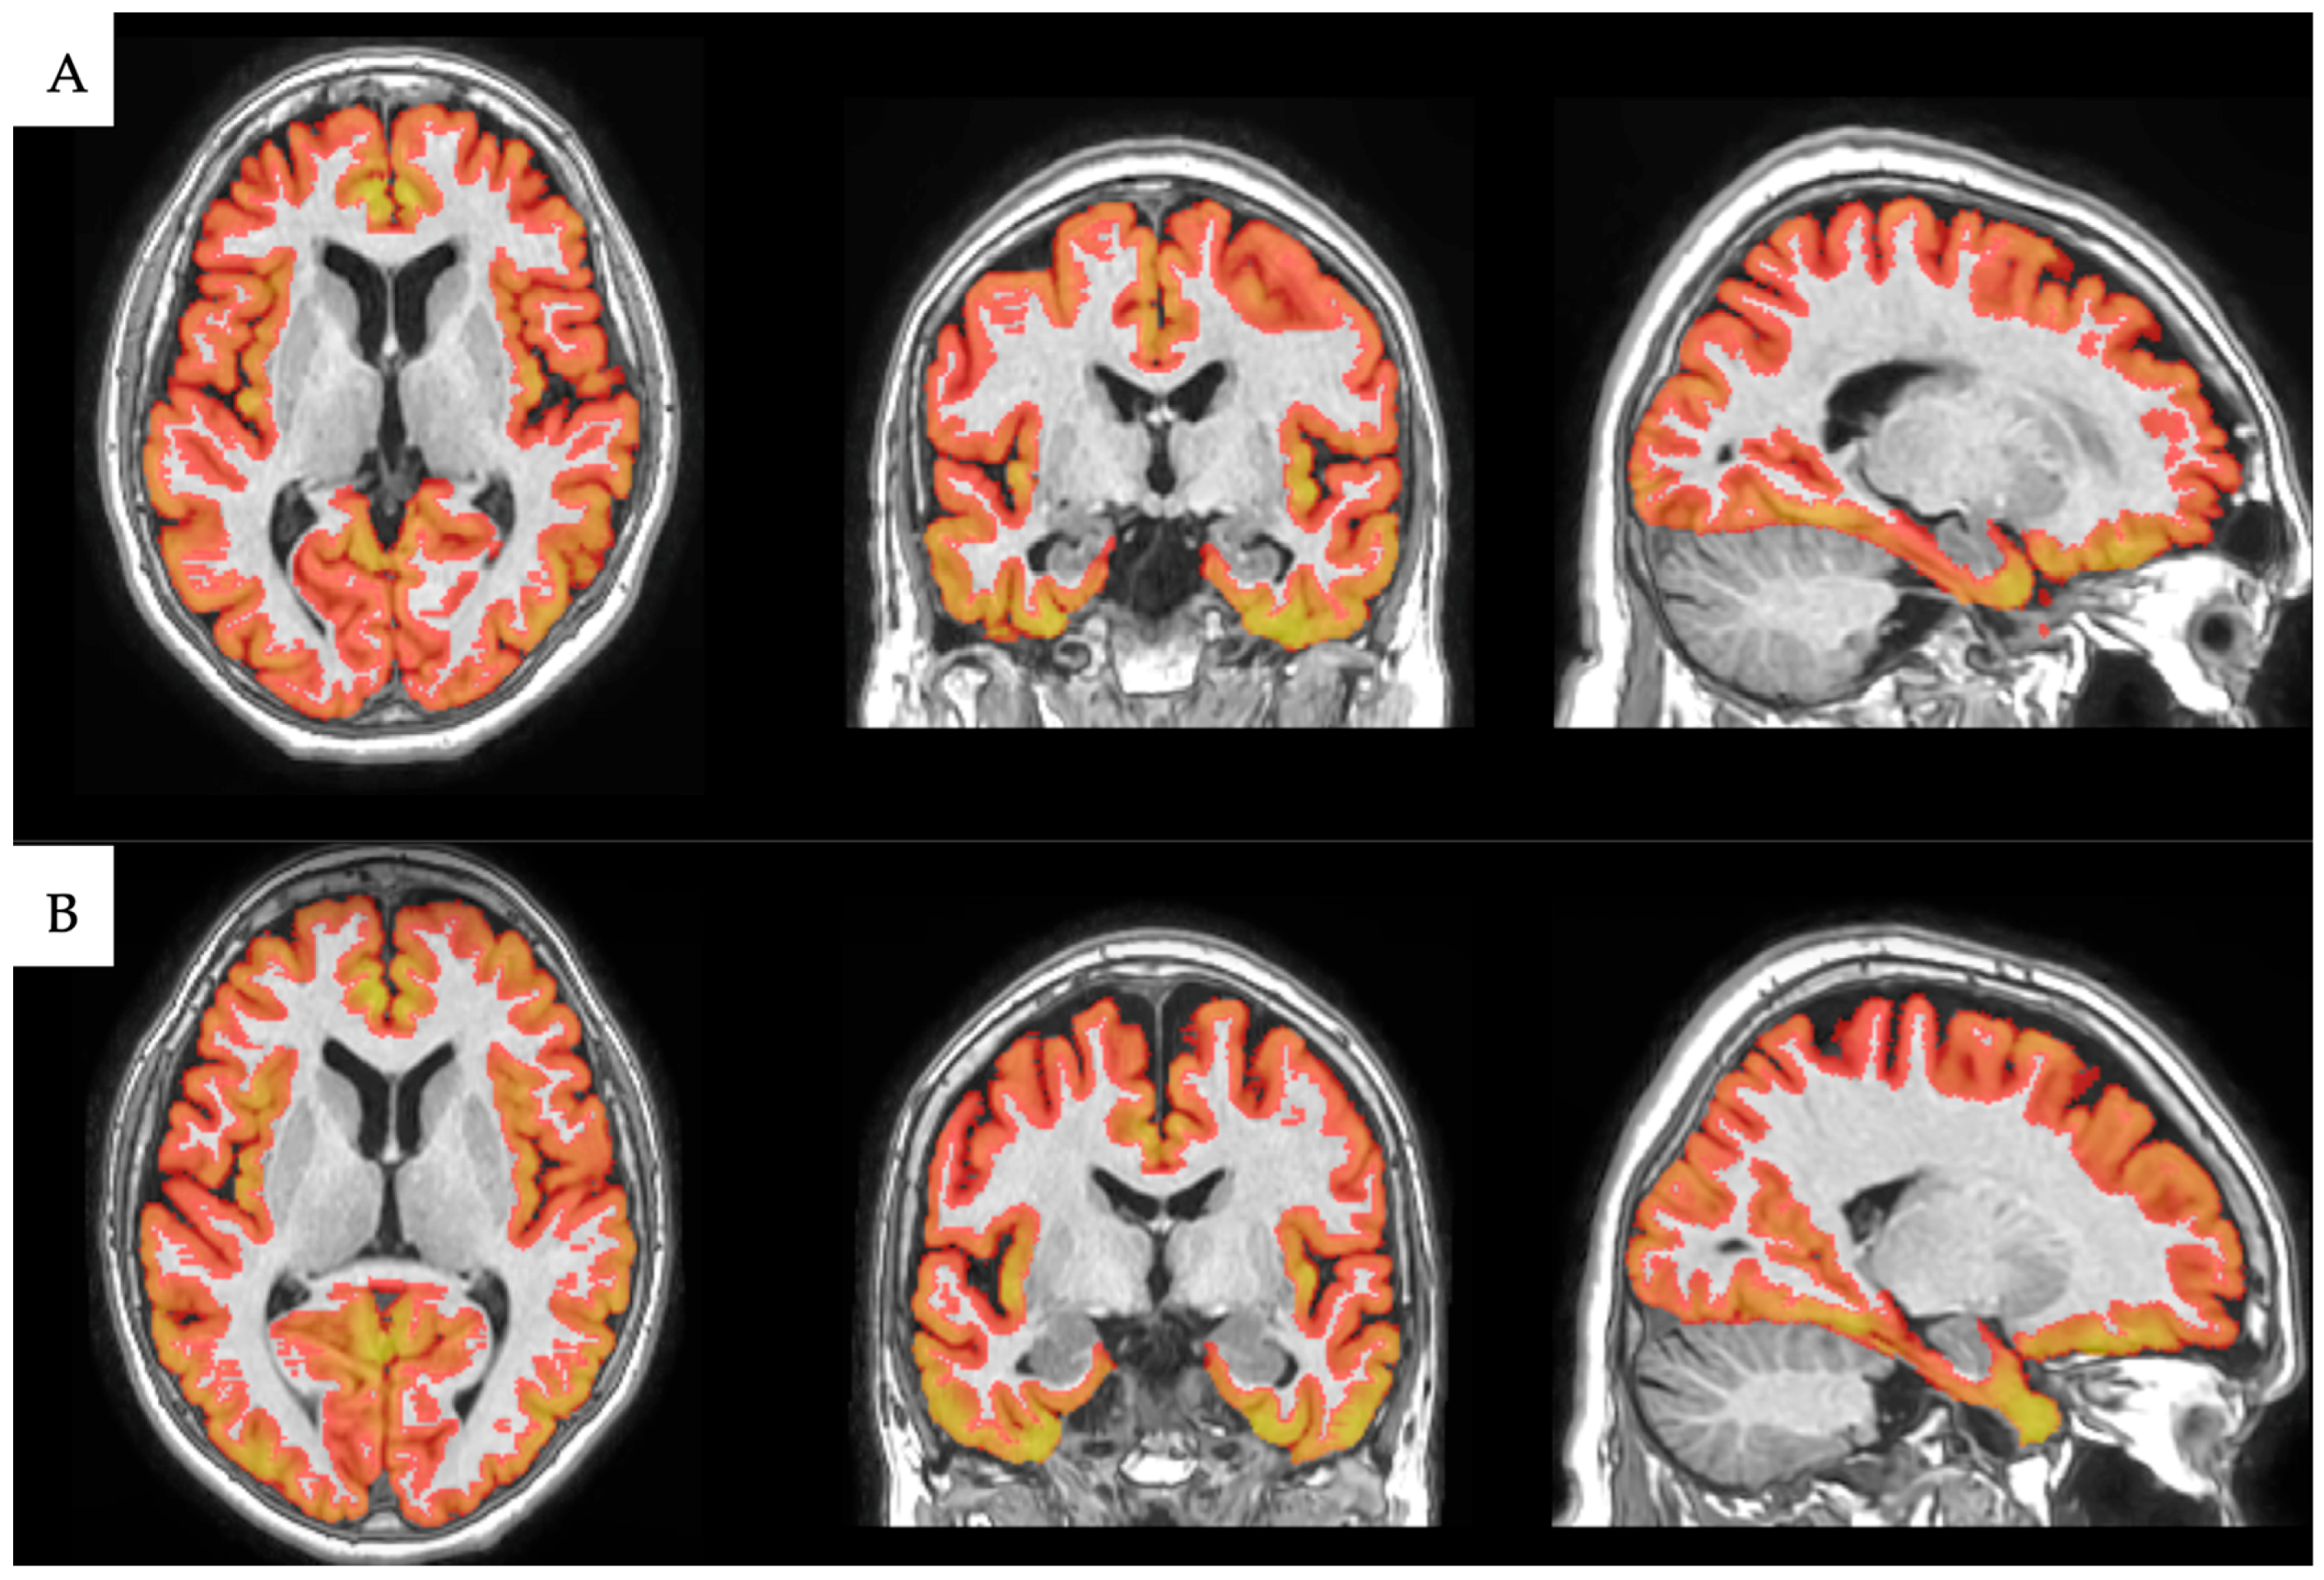

2.3. Image Processing

Volumetric Analysis with volBrain